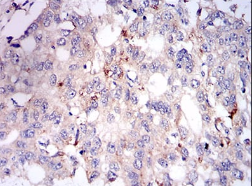

PLIN2 Mouse Monoclonal antibody[2C5A3]

IHC    1/200 - 1/1000